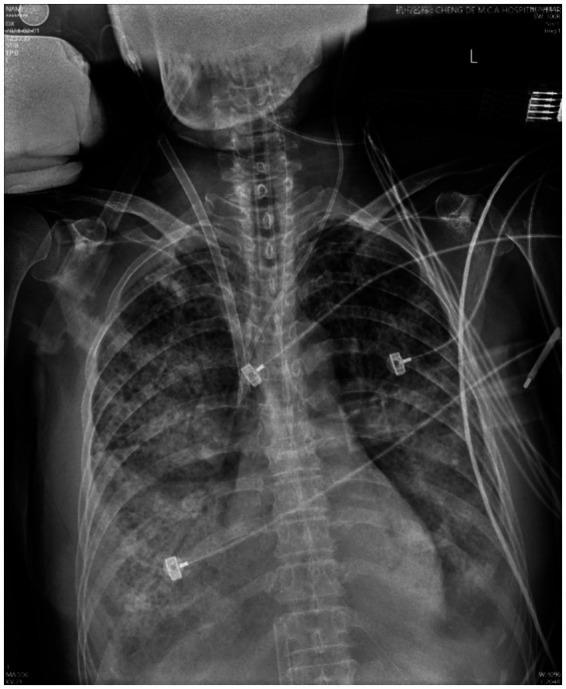

Co-infection of the influenza B virus with other bacterial pathogens is a significant contributor to the high pathogenicity and mortality associated with influenza B. The most common bacterial co-infections are caused by and species. In this case report, we describe the clinical symptoms and treatment of a 69-year-old woman who developed fulminant pneumonia secondary to infection following initial influenza B virus infection. This case emphasizes the importance of early recognition and the use of extracorporeal membrane oxygenation in treating fatal pneumonia caused by co-infection with methicillin-sensitive and influenza B virus. We conclude that this case provides valuable insights into the severe complications of influenza co-infections and underscores the role of extracorporeal membrane oxygenation in the management of fulminant pneumonia.

乙型流感病毒与其他细菌病原体的共同感染是导致乙型流感高致病性和高死亡率的重要因素。最常见的细菌共同感染是由 和 物种引起的。在本病例报告中,我们描述了一名69岁女性的临床症状和治疗情况,该患者在最初感染乙型流感病毒后继发 感染,进而发展为暴发性肺炎。本病例强调了早期识别以及使用体外膜肺氧合治疗由甲氧西林敏感 和乙型流感病毒共同感染所致致命性肺炎的重要性。我们得出结论,该病例为流感合并感染的严重并发症提供了有价值的见解,并强调了体外膜肺氧合在暴发性肺炎管理中的作用。